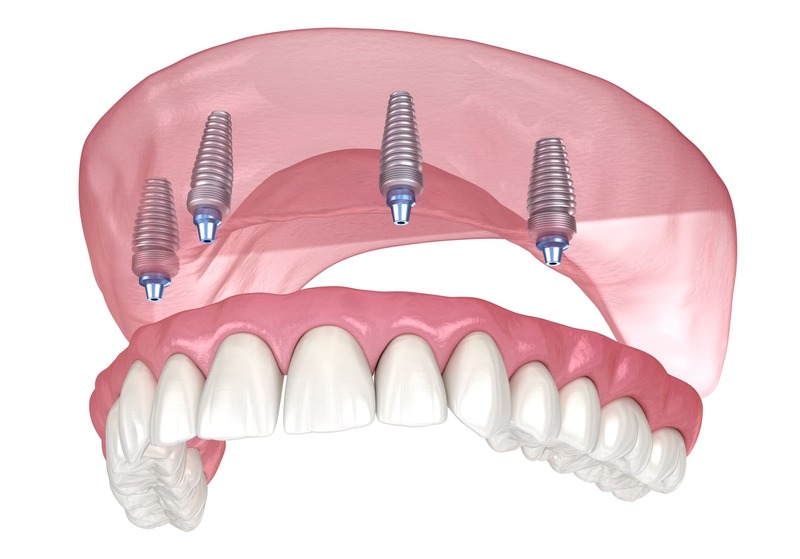

The All on 4 dental implant procedure typically takes several appointments over the course of several months. The exact duration will depend on the individual case and the number of implants needed.